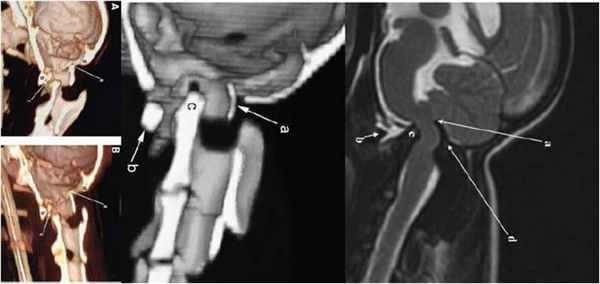

а - Основные костные структуры, составляющие шейно-затылочное сочленение.

б - Срез через затылочную кость, демонстрирующий разницу толщины срединного затылочного гребня и более тонкой чешуи затылочной кости.

Независимо от техники операции, применяемой при хирургической стабилизации шейно-затылочного сочленения, для успешного исхода необходимо соблюдать меры предосторожности в операционной. В частности, перед выполнением операции, хирургу необходимо определить оптимальное положение шейно-затылочного сочленения. Филлипс (Phillips) и др. писали, что «нейтральное» положение черепа относительно шейных позвонков является наиболее функциональным, и определили, что «нейтральным» рентгенологически является положение, при котором голова выровнена в сагиттальном направлении и находится в стандартном положении снятия боковой рентгенограммы.

Для описания данного положения указанные авторы использовали шейно-затылочный угол (относительно линии МакРэя [McRae] и верхнего края пластинки дуги позвонка С3) и расстояние между костными структурами. Кроме того, Таками (Takami) и др. определили, что правильное выравнивание угла краниовертебрального сочленения помогает предотвратить возникновение послеоперационных осложнений, таких как подвывих шейного отдела ниже осевого позвонка, нарушение глотания и дыхания.